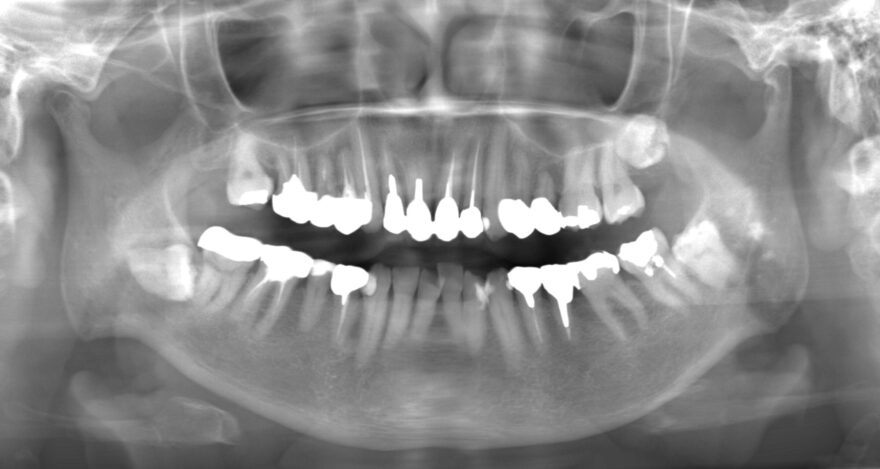

初診時のレントゲン写真

治療中のデジタルデータ治療後のレントゲン写真

合計3本のインプラントが入りました。